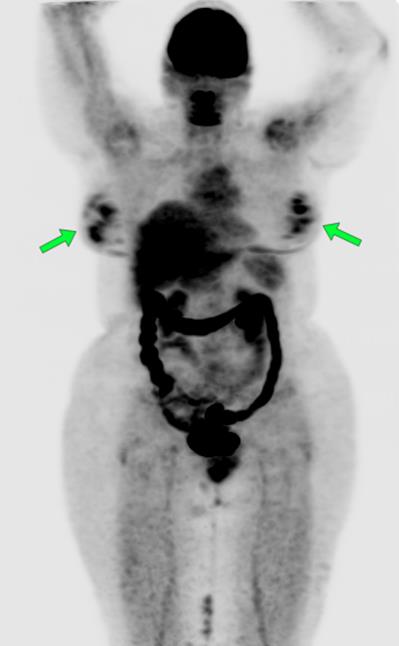

The most common cause of skin metastases in adult women is primary breast carcinoma, which comprises about 70% of cases [1]. Skin metastases have non-specific clinical appearances, making it challenging to differentiate them from other benign conditions [1]. We present a case of a 52-year-old female with type II diabetes and a three-month history of refractory skin lesions who did not respond to anti-inflammatory treatment. The patient subsequently complained of a right breast lump, evaluation of which led to the diagnosis of bilateral synchronous invasive lobular carcinoma.